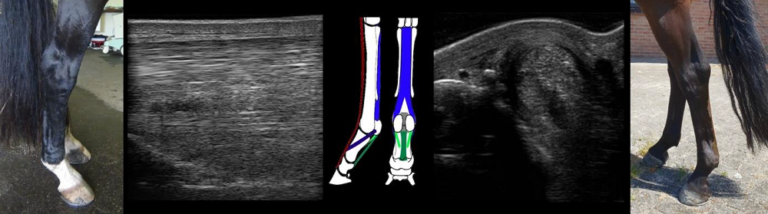

Iedere pees in het paardenlichaam kan geblesseerd raken, maar de belangrijkste pezen waar regelmatig blessures aan optreden lopen aan de achterzijde van het pijpbeen. Dit zijn de oppervlakkige buiger (1.), de diepe buiger (2.), het check ligament (3.) en de interosseus (tussenpees) (4.), aan de achterzijde van het pijpbeen (5.).

De oppervlakkige buiger (1.) loopt aan de achterzijde van het been, direct onder de huid. De diepe buiger (2.) loopt voor de oppervlakkige buiger langs, kruist met de oppervlakkige buiger en hecht aan op de onderzijde van het hoefbeen. Het check ligament (3.) begint aan de achterzijde van de voorknie en smelt samen met de diepe buiger ongeveer halverwege de pijp. De interosseus (4.) ligt tegen de achterzijde van het pijpbeen aan en splitst zich verder naar beneden in twee schenkels die aanhechten op de sesambeentjes (zie afbeeldingen). Verschillende sterke, korte annulaire ligamenten (ringbanden) helpen om de pezen op hun plaats te houden in gebieden met veel beweging, zoals gewrichten.

Echobeeld van check ligament: